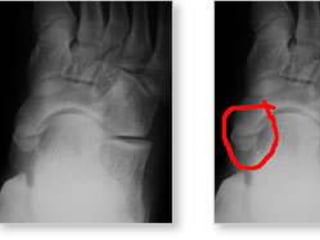

Radiography

• Special view - 45 degree eversion oblique for

accessory navicular bone

• Antero-Posterior view and Lateral weight bearing

Radiological types

• TypeI–Small ossicle in the substance of Tibialis Posterior

tendon (os tibiale externum or naviculam secondorium )

• Type II –Triangular frangment larger than type I connected

to navicular bone by a cartilaginous synchondrosis

• Type III – Cornuate navicular resulting from fusion of the

accessory navicular with main body of navicular